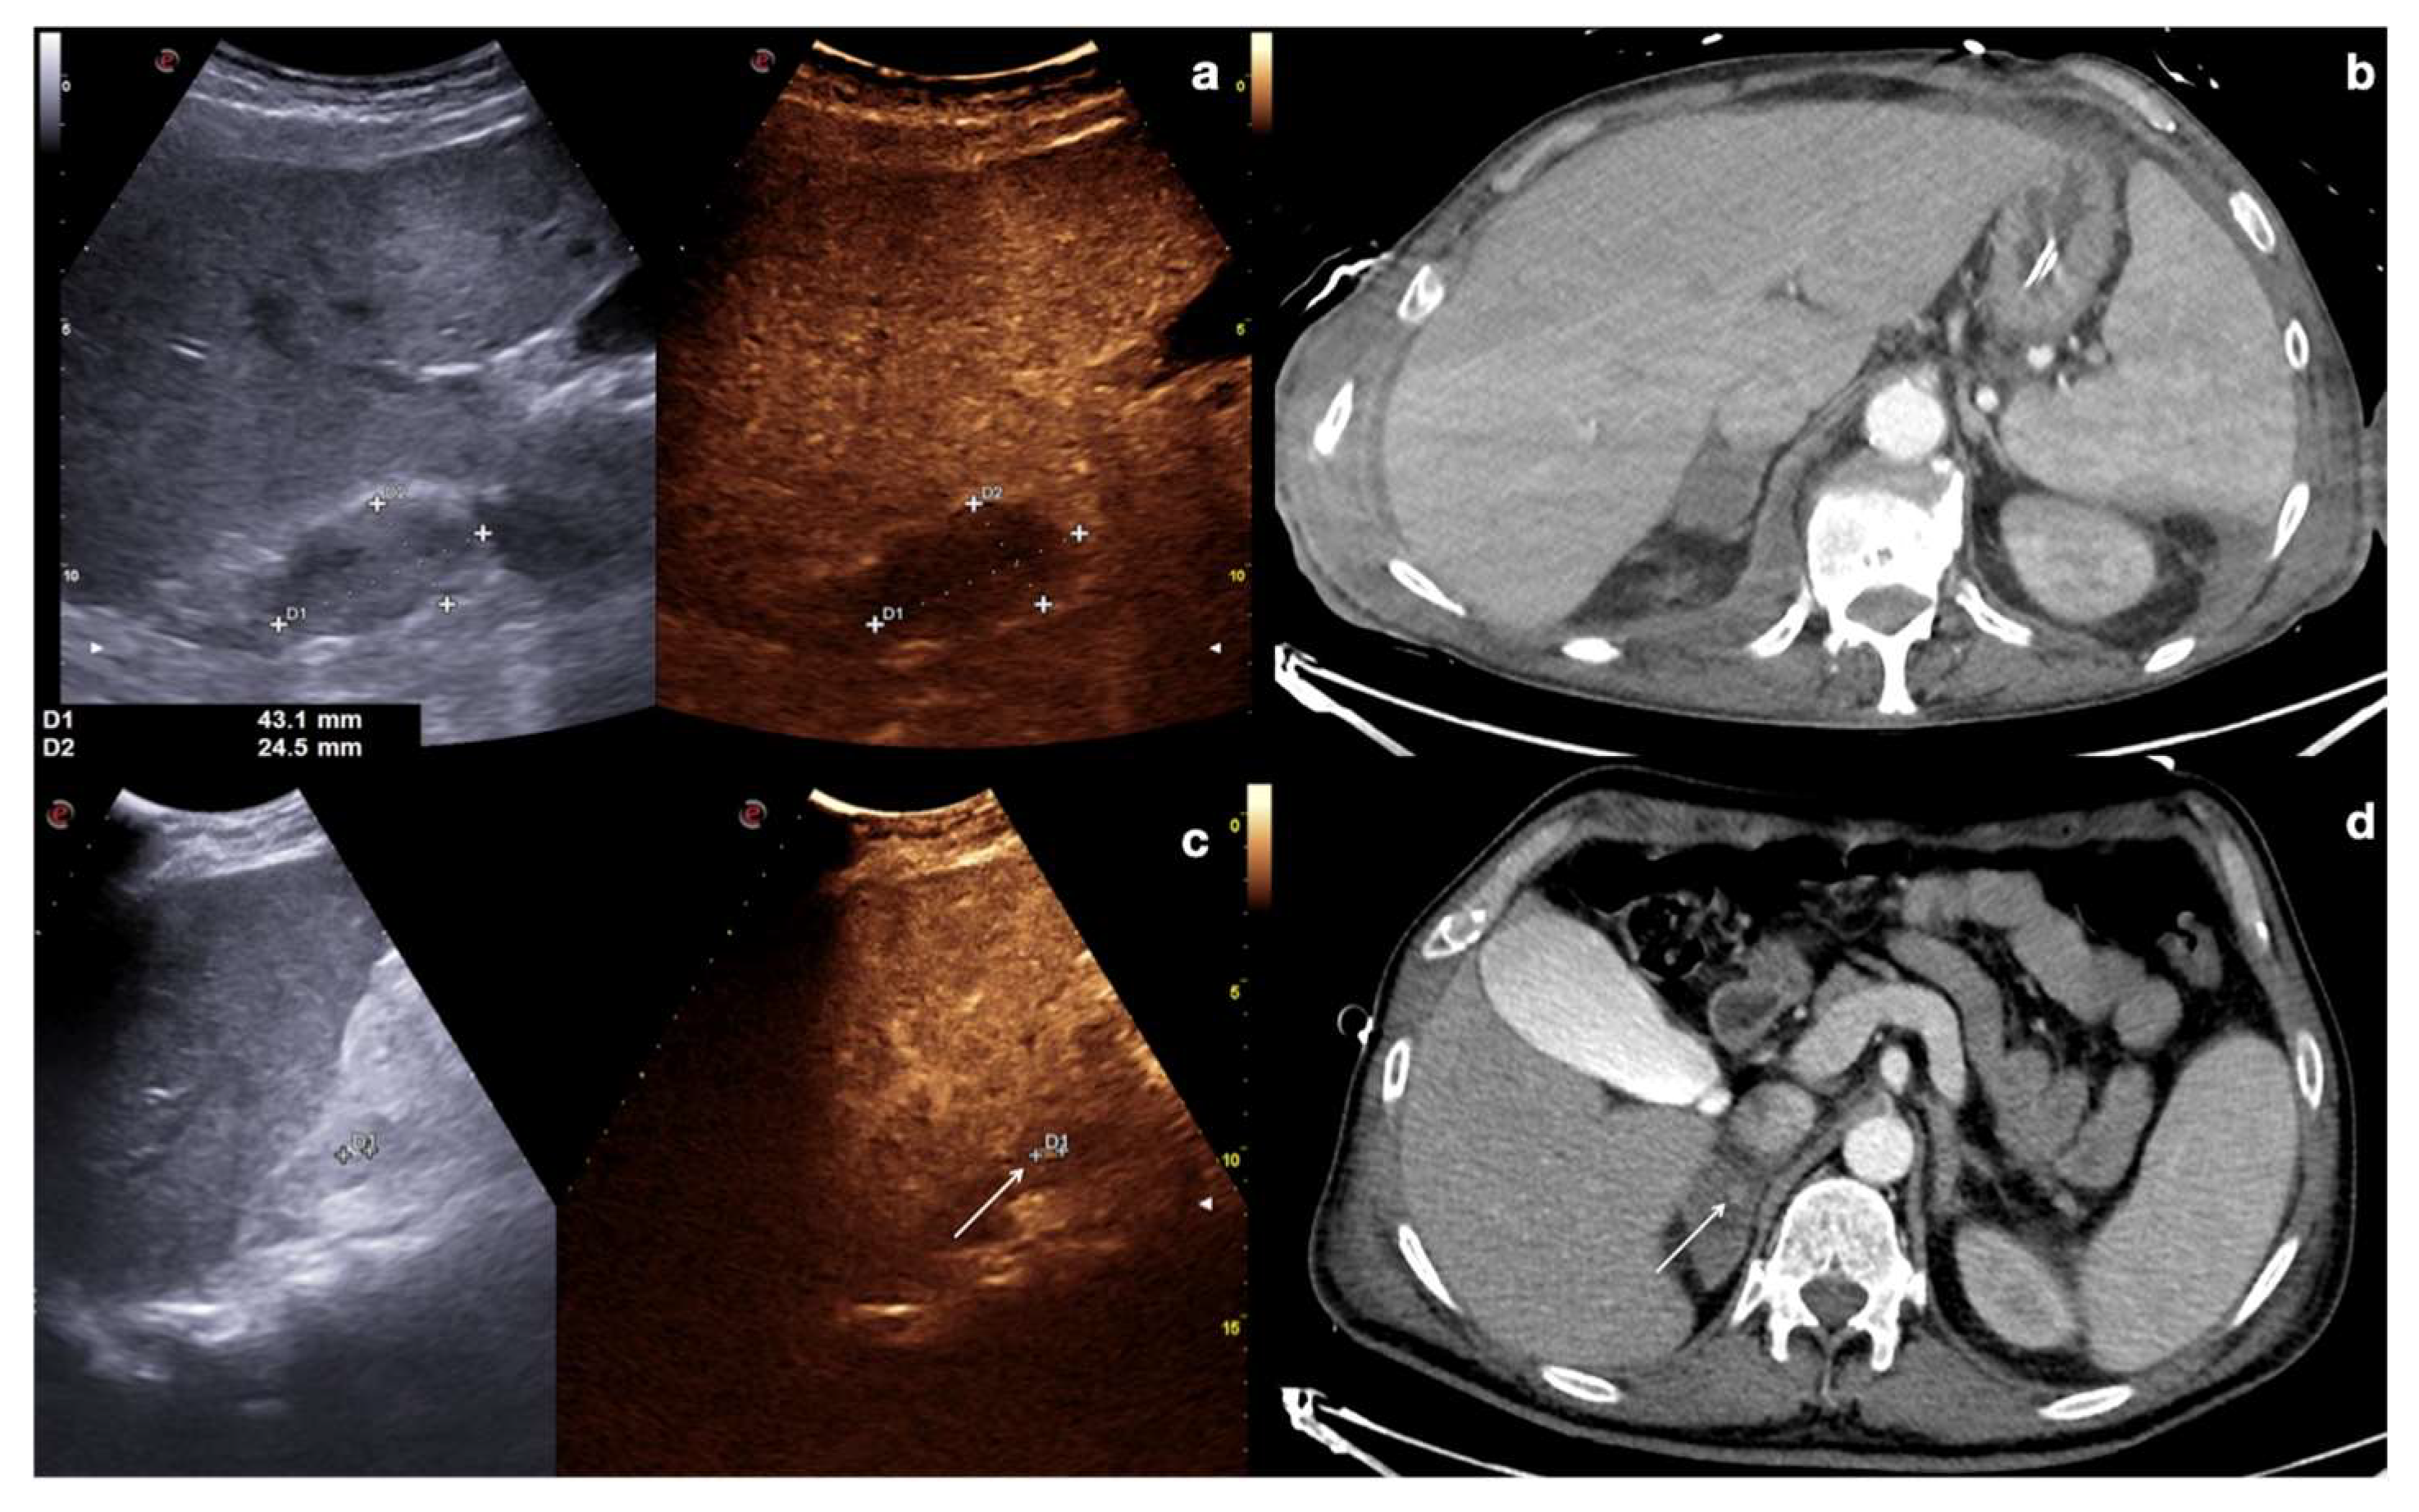

4.1. Step 1

4.2. Step 2

4.3. Step 3

4.4. Step 4

4.5. Step 5